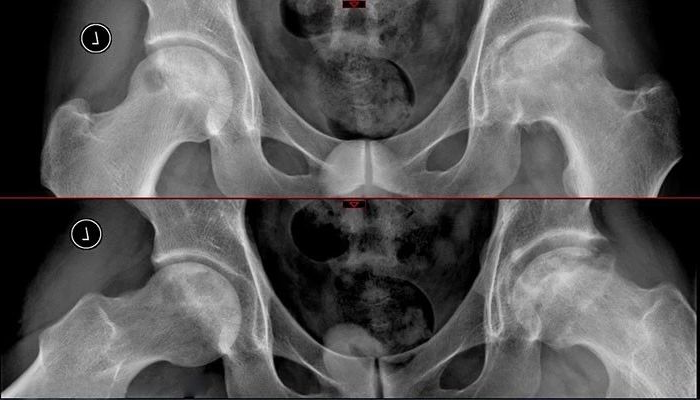

这是一位30岁的男性患者,病人自述有15年的饮酒史,右胯(髋)关节疼痛、活动受限1年、左髋关节疼痛1年。临床诊断:双侧股骨头坏死。

左侧股骨头内大面积囊性变,波及外侧柱。

CT影像证实右侧股骨头关节面几近碎裂,股骨头前侧可见大面积囊性变空洞,髋臼缘及股骨头边缘可见骨质增生;左侧股骨头囊性变范围也非常大,几乎就剩余一个空壳,塌陷危险性非常高。